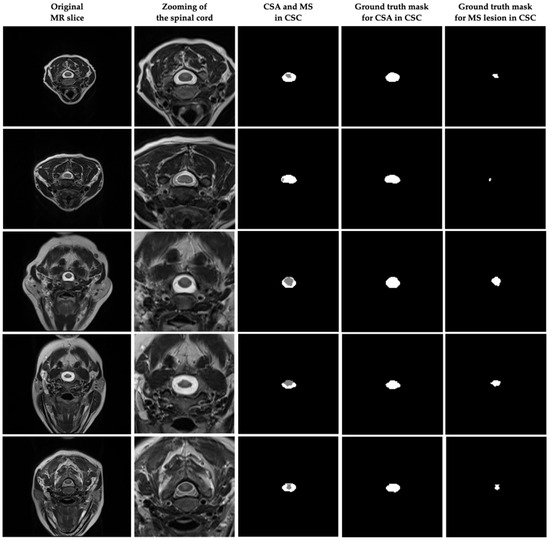

The images in the scans obtained from the SIEMENS Spectra Magnetom 3T device as DICOM in the dataset were 320 × 250 pixels, and the slice thickness in the scans was 4 mm. For the cross-sectional area (CSA) and MS lesions in the images of the MR scans forming the dataset, ground truth masks were manually determined by two different radiologists using ITK-SNAP 4.0 software [40]. This resulted in a total of 231 suitable slices for CSA and MS in the axial plane. Preprocessing steps and data augmentation techniques were used to train the model, and performance analysis was performed by dividing the data into training, validation, and test sets. Figure 2 shows some of the original MR images in the dataset and the ground truth masks of the CSA and MS lesions in CSC. In addition, it was approved by the decision of the Clinical Research Ethics Committee of Akdeniz University Faculty of Medicine dated 15 September 2021 and numbered KAEK-644 that there are no ethical objections to conducting this study and creating the dataset.